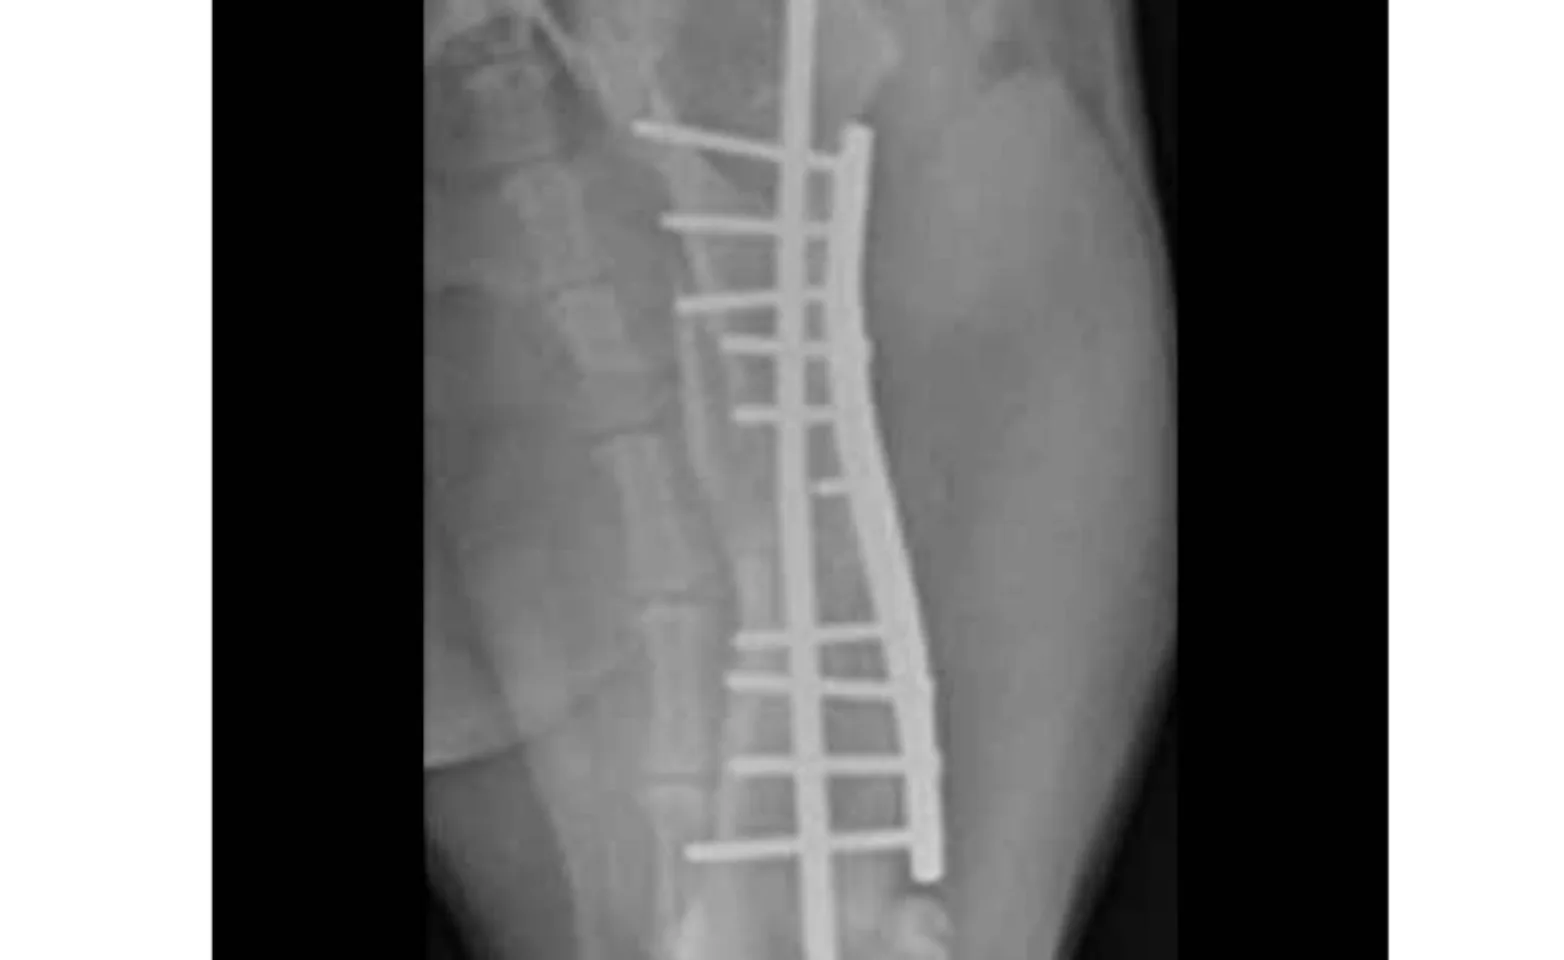

Biologic osteosynthesis is a concept of fracture healing based on minimal disruption of the soft tissues around a fracture. Iatrogenic vascular damage to the fragments can be avoided by closed reduction and placement of an external fixator. Alternatively, an open approach and bridging of the fracture site with a buttress plate or plate-rod combination may be used. A plate used in buttress fashion provides rigid fixation of the proximal and distal bone fragments. The addition of a single intramedullary pin decreases strain and increases the fatigue life of the plate. In such cases, prolonged surgical time and tissue injury necessary for reduction and fixation of small fragments is avoided.